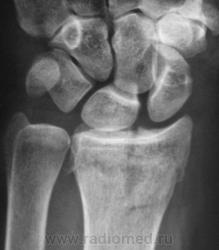

Случай 2. Пациент направлен на рентгенографию лучезапястного сустава.

А вот как трактовать в случае 2 перелом?

В случае 2 - на мой взгляд внутрисуставной перелом задненаружного края дист эпифиза лучевой кости.

Что за +ткань по нар краю эпифиза луча - сложно сказать, мож ломал раньше.